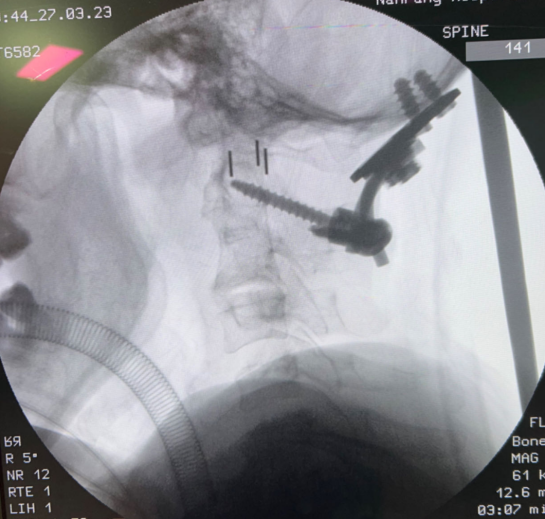

病例二:

簡介:

使用拱(gong)形枕骨(gu)板(ban)配合融合器(qi)進行內固定,術后隨訪效(xiao)果良好。